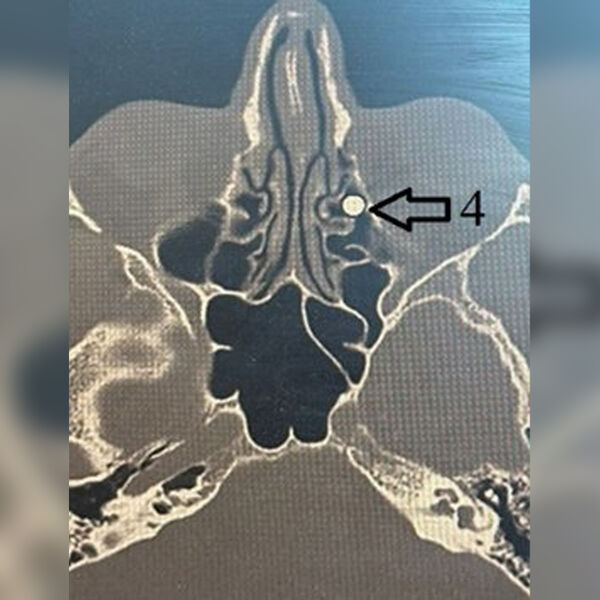

Пациент поступил с ранением из травматического ружья. Пуля диаметром 4,5 мм вошла через внутренний угол глаза, прошла через глазницу и застряла в носу. Сначала мужчине провели операцию по восстановлению тканей глаза, после чего передали пациента врачам лор-отделения клиники.